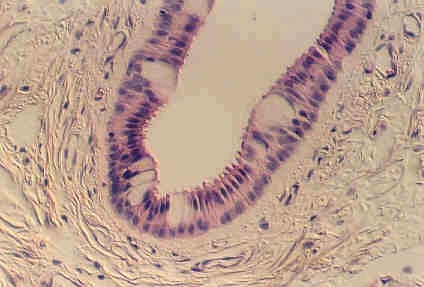

Stratified Columnar epithelium is rare. One place you can find it is in the largest ducts of salivary glands (parotid, submandibular, etc). The basal layer of cells are cuboidal cells and the layer nearest the apical surface includes columnar cells. The large droplets are mucus, in Goblet cells. This also illustrates the fact that epithelia are classified according to the cells nearest the lumen, in this case columnar.

Below is another view of a large (excretory) duct of a salivary gland showing the mucin in Goblet cells after a special stain. What might be the advantages of an epithelium that has a basal cuboidal cell layer and an apical columnar cell layer?